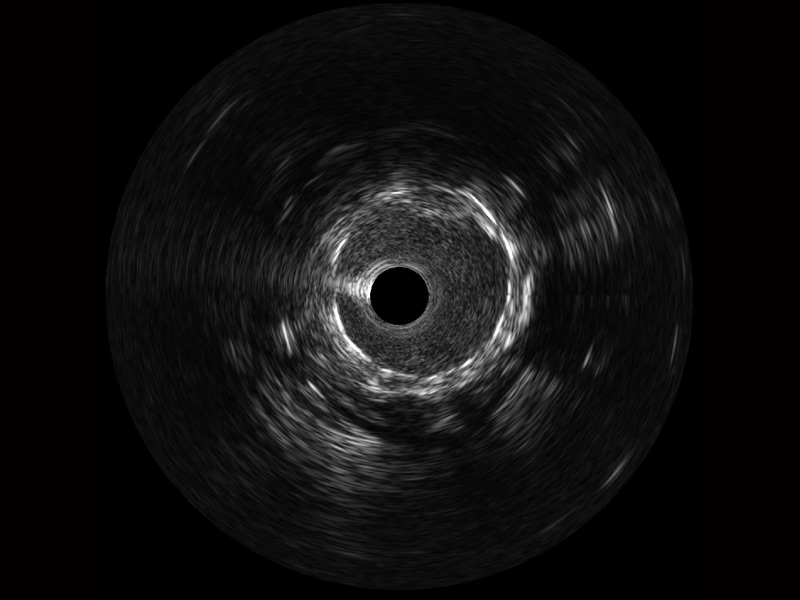

传统IVUS图像

对比传统IVUS导管成像,九州酷游宽频IVUS图像的近场支架梁显影更细腻,远场中膜外血管仍清晰可辨,兼顾远中近,兼顾分辨力与穿透深度